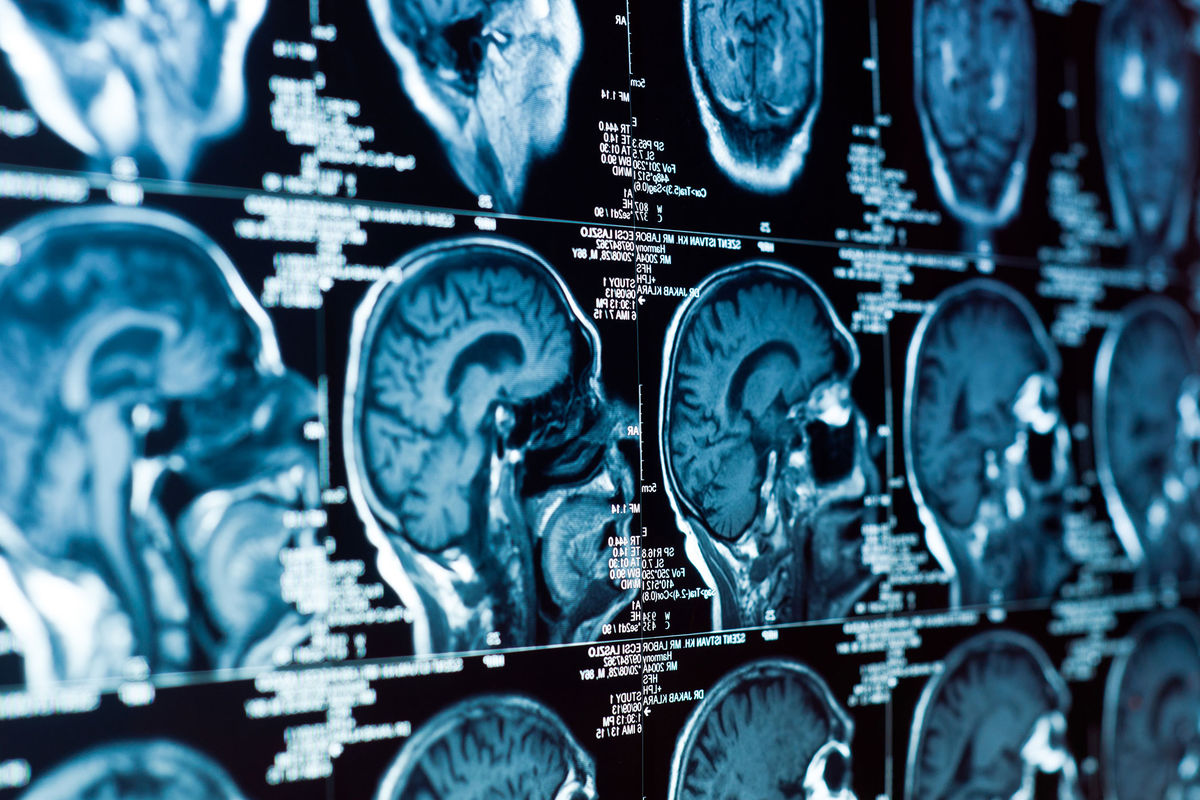

Чтобы подтвердить механизм, исследователи использовали рентгеновскую кристаллографию и визуализировали, как гидралазин связывается с ферментом. Затем препарат протестировали на клетках глиобластомы, и результаты подтвердили: блокирование АДО нарушает цикл адаптации к гипоксии.